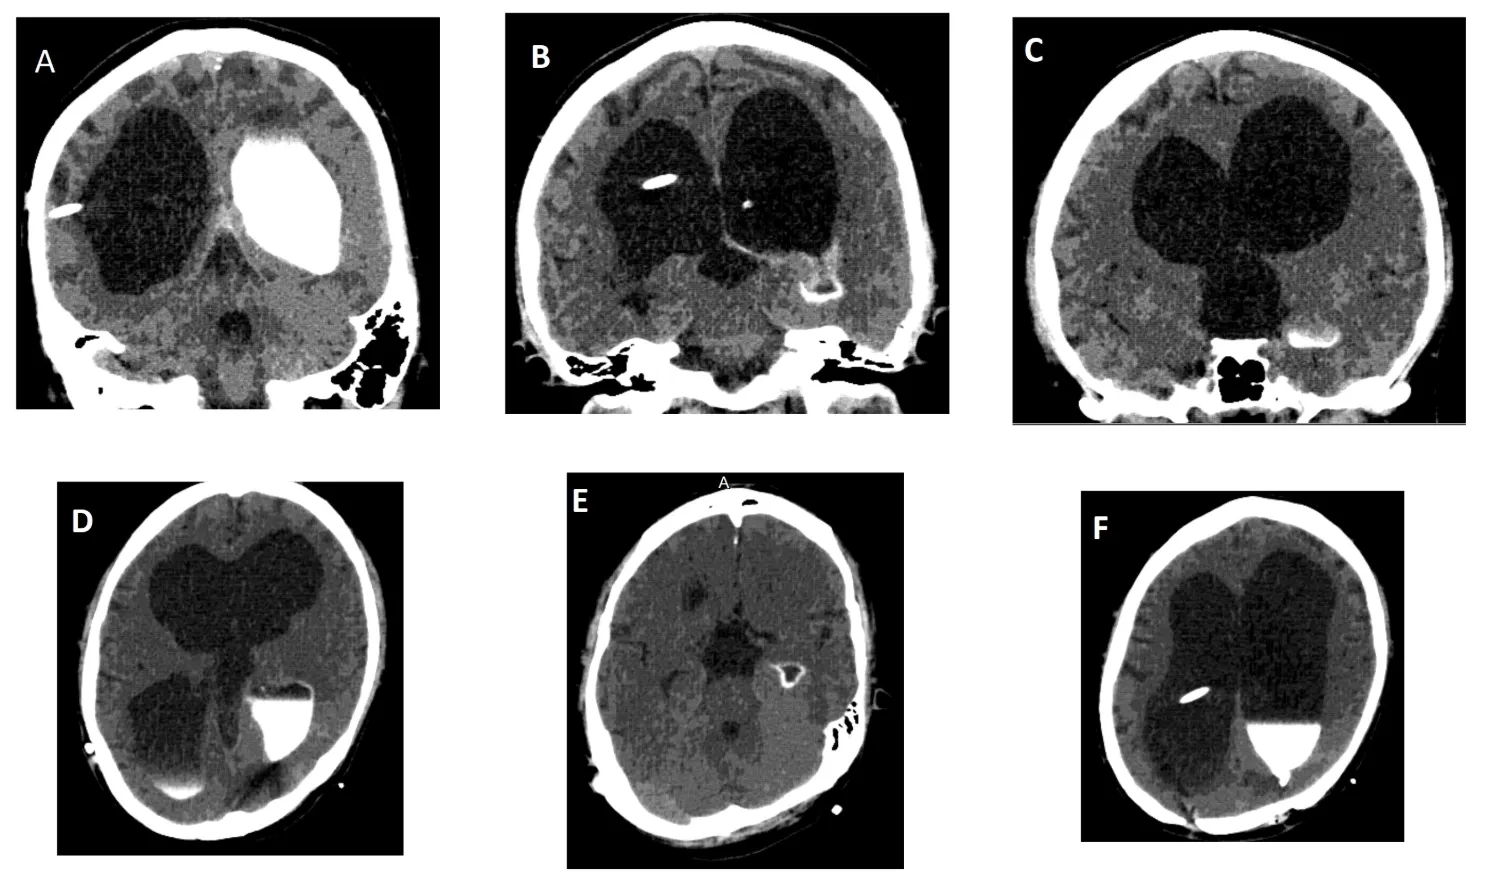

He recovered neurologically within 24 hours of admission slowly but remained extremely lethargic with no new lateralizing neurological deficits. It was decided to perform a CT ventriculogram to study CSF cells/ chemistry and culture, and assess the "trapped third ventricle", as his cardiac pacemaker precluded an MRI scan of brain with cine flow studies for CSF flow across the foramen of Monro and aqueduct.

CT ventriculogram demonstrated a trapped third ventricle secondary to bilateral foramen of Monro obstruction or occlusion, with intact fourth ventricle. Figure 1 shows cranial CT with triventricular hydrocephalus and right VP shunt. The contrast dye placed in the frontal horn of lateral ventricle was not seen entering the third ventricle at all, even on follow up scans shown in Figures 2 and 3. No contrast egress was noted into the rounded enlarged third ventricle. Eventually the dye cleared off the lateral ventricles as demonstrated in Figure 4 done 24 hours after contrast injection. Given the fact that the patient improved neurologically and there was a possibility of arrested hydrocephalus, he was started on a higher dose of Keppra and he was discharged home at his neurologic baseline exam.